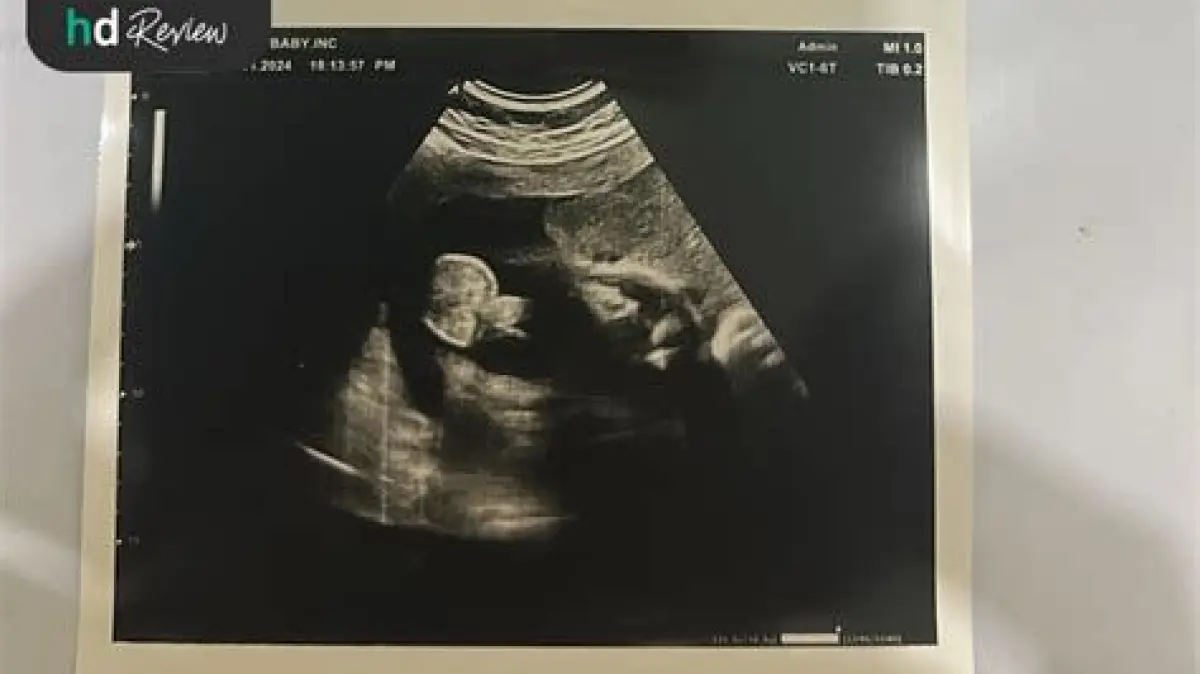

USG 2D: Apakah Cukup Andal Deteksi Kelainan Janin?

USG 2 dimensi (2D) adalah metode pemeriksaan kehamilan yang paling umum dilakukan. Namun, seringkali muncul pertanyaan, seberapa efektifkah USG 2D dalam mendeteksi kelainan pada janin? Apakah cukup akurat, atau perlu pemeriksaan lanjutan dengan teknologi yang lebih canggih? Kami akan mengupas tuntas informasinya untuk Anda.

USG 2D memberikan gambaran dua dimensi dari janin. Melalui pemeriksaan ini, dokter dapat melihat:

- Struktur Anatomi Dasar: Seperti kepala, tulang belakang, anggota badan, dan organ-organ utama.

- Posisi Janin: Mengetahui letak janin dalam rahim.

- Jumlah Janin: Mendeteksi kehamilan tunggal atau ganda.

- Detak Jantung Janin: Memastikan jantung janin berdetak normal.

- Jumlah Air Ketuban: Memantau volume cairan ketuban yang penting bagi perkembangan janin.

- Plasenta: Menilai posisi dan kondisi plasenta.